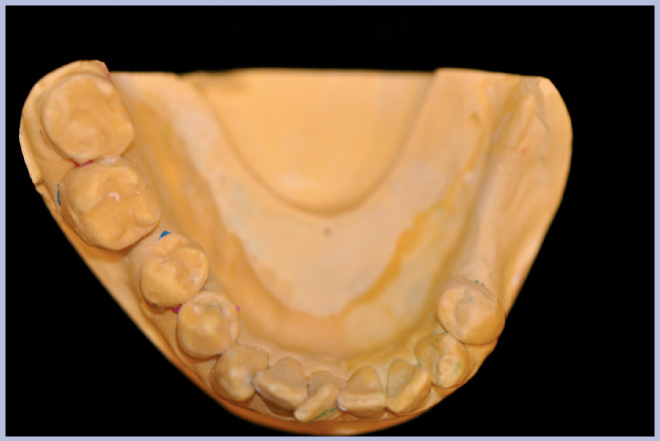

Per riabilitare la masticazione del terzo quadrante, con osso gravemente atrofico, si procede allo studio del caso con esame radiologico 3D e posizionamento virtuale di impianti Exacone® Leone. La prima valutazione è stata eseguita con il software dell’apparecchio radiografico Cone Beam presente in studio. Dopo aver verificato che la quantità di osso residuo fosse sufficiente all’inserimento di due impianti, seppur di dimensioni ridotte, in sede 3.5 e 3.6 senza l’ausilio di tecniche di rigenerazione ossea (Figg. 1-3), si richiede al laboratorio di confezionare una mascherina radiologica con ceratura diagnostica radiopaca e repere standardizzato a livello incisale come da protocollo Leone (Figg. 4, 5). Si verifica quindi clinicamente l’assenza di mobilità della mascherina dopo il posizionamento nel cavo orale del paziente (Figg. 6, 7). Si effettua una CBCT con la mascherina in posizione e l’esame viene inviato in formato DICOM all’azienda Leone assieme al modello master della paziente. L’azienda provvede quindi ad inviare agli Autori il software 3Diagnosys (software di progettazione) in licenza monopaziente con caricati i file DICOM ricevuti; il software viene quindi utilizzato per la progettazione definitiva del caso (Figg. 8-12).

- Figg. 4, 5 – Realizzazione della mascherina radiologica

- Fig. 5